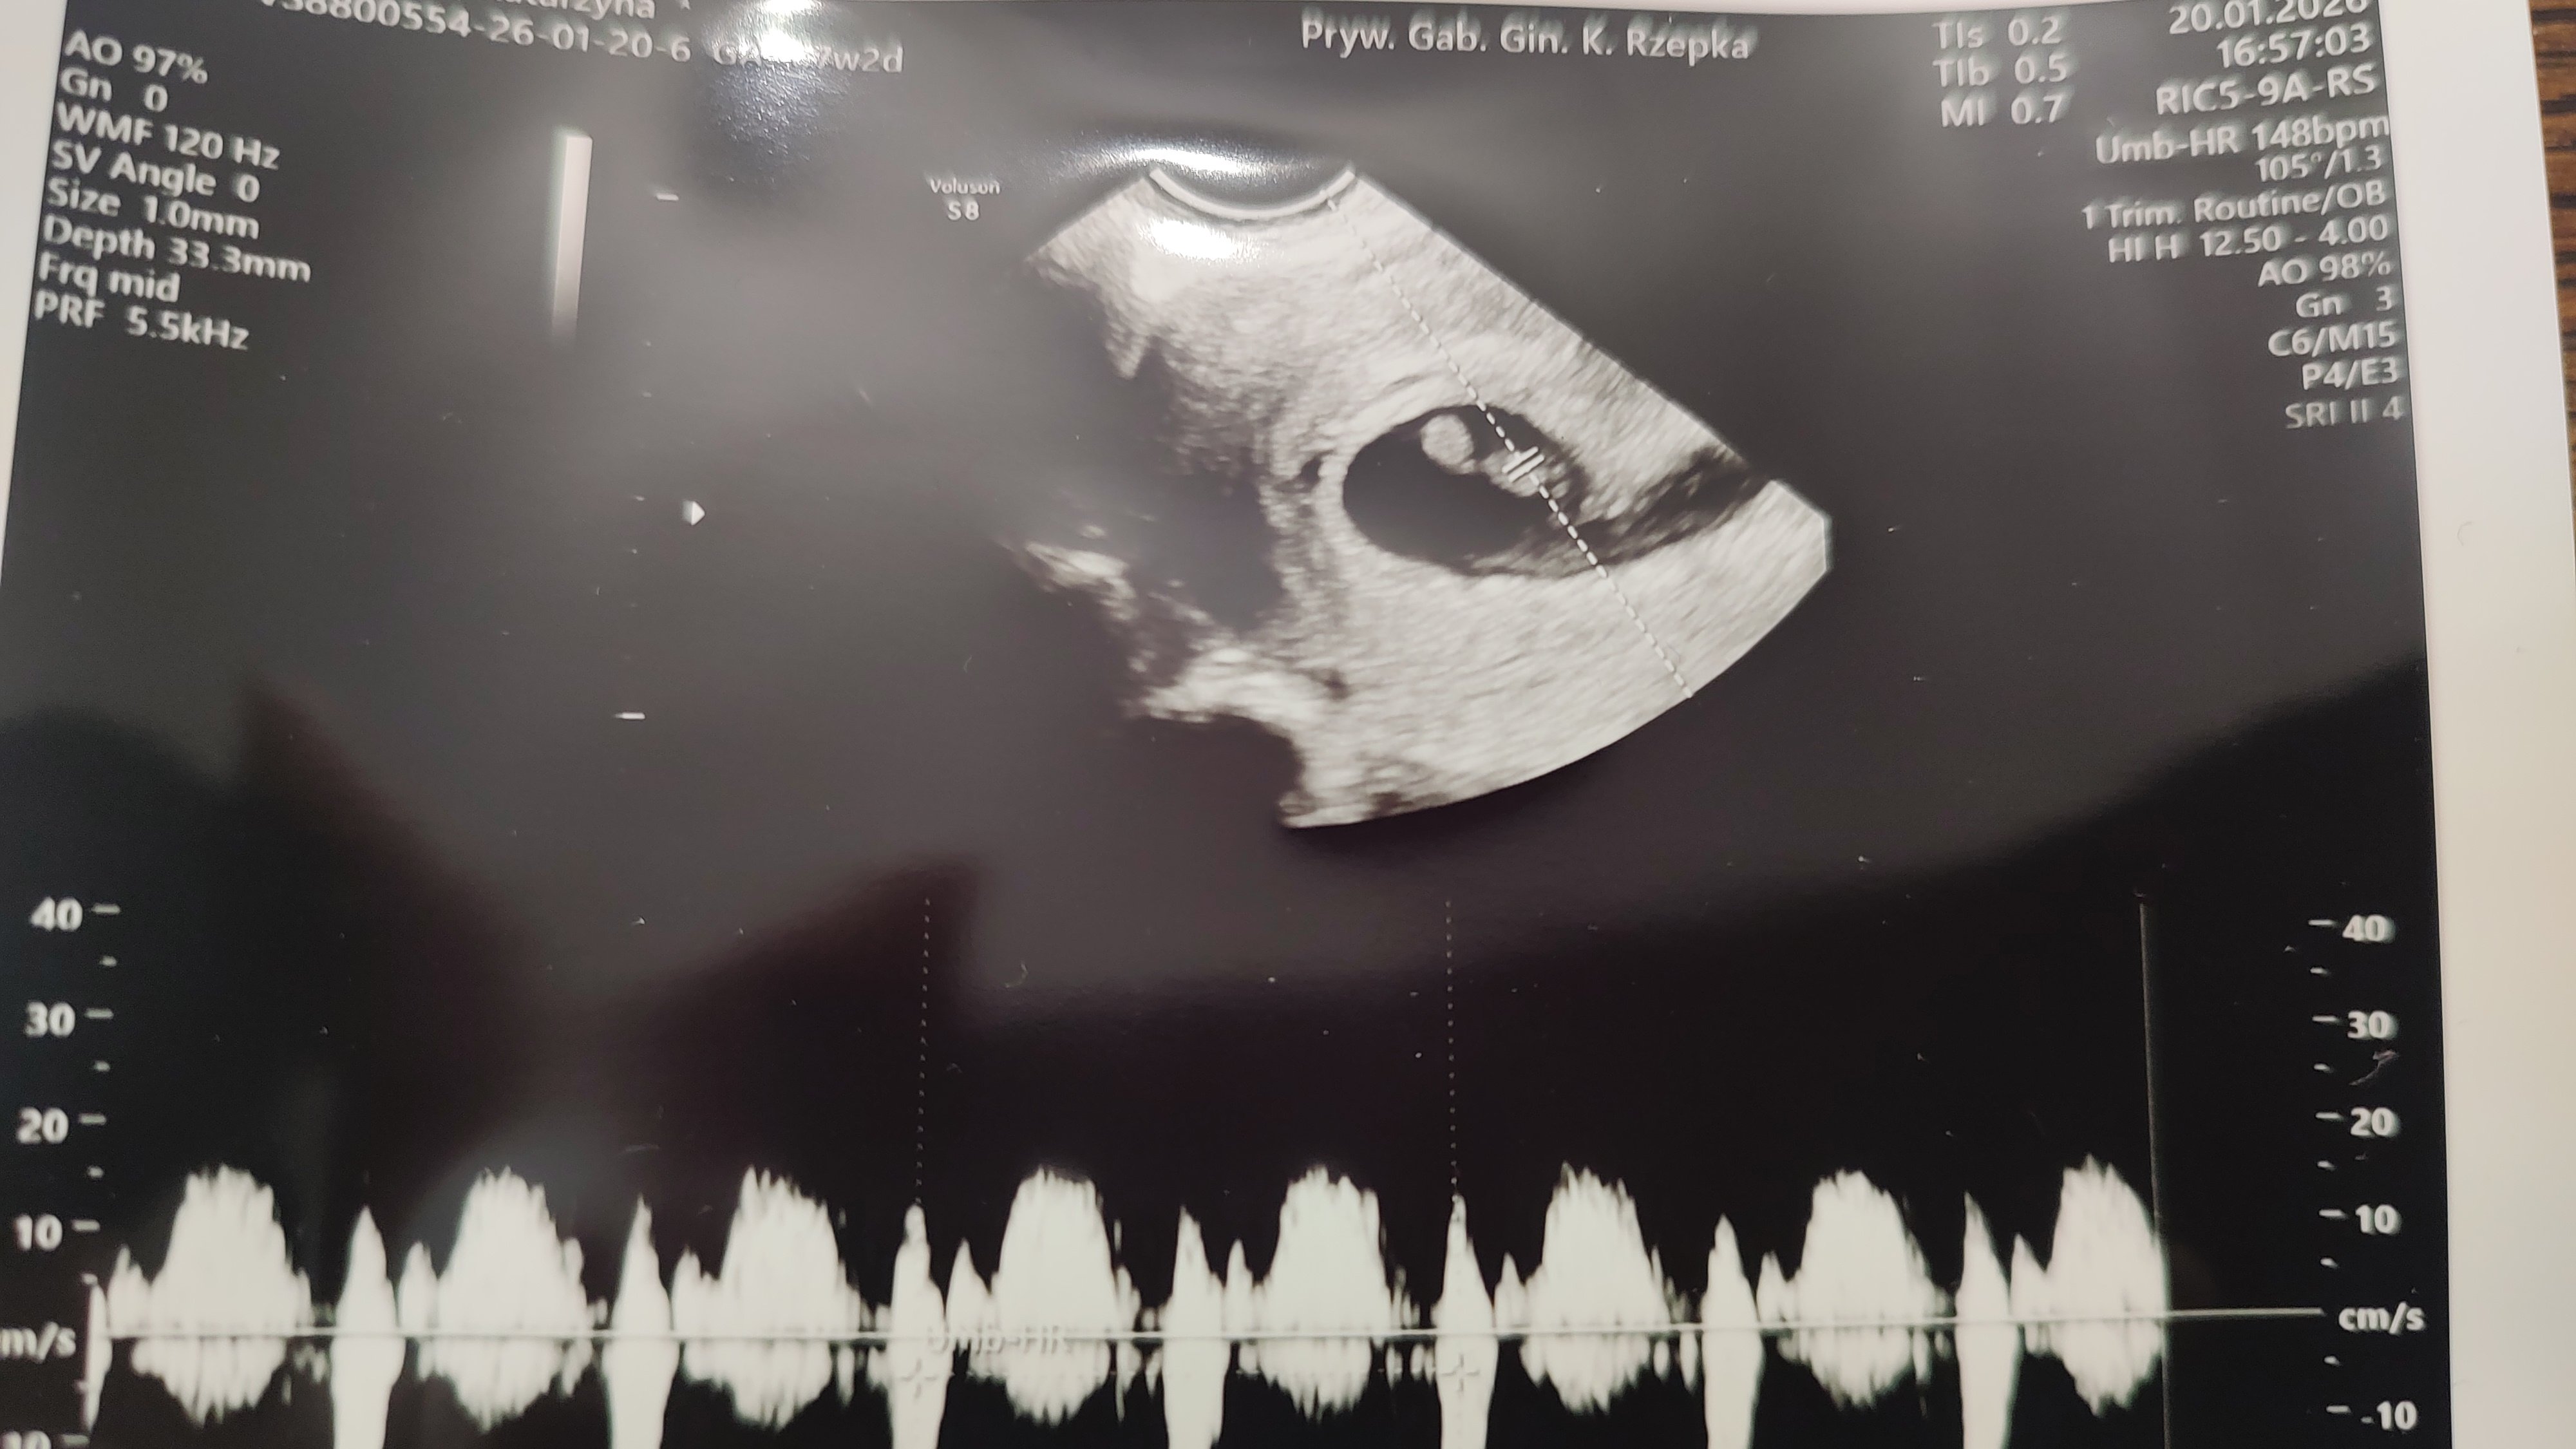

W czwartek z OM wychodziło 7+2 a z USG po pojawieniu się zarodka 6+1

U mnie na wydruku jest akcja serca. Ale może być tylko opisowo, jak macie wątpliwości szukajcie coś o opisie BMP 😀 ale skoro lekarz założył kartę to musiał wiedzieć serducho.

• IMG_20260120_205229288.jpg

IMG_20260120_205229288.jpg

678,3 KB · Wyświetleń: 62